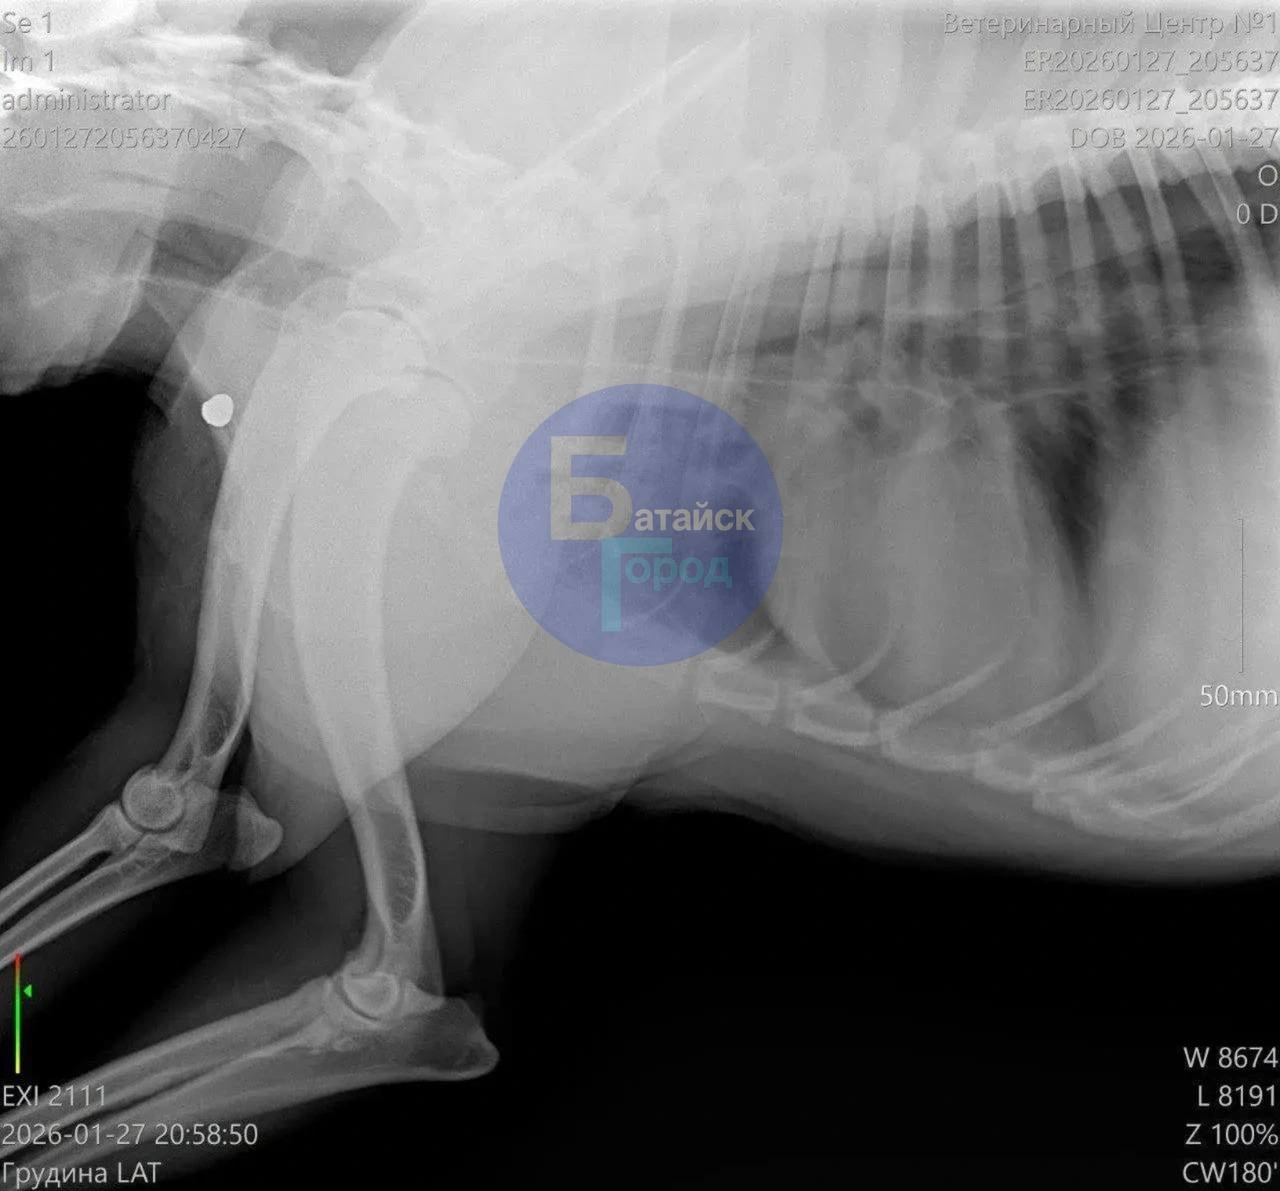

По сообщению, раненого пса обнаружили местные жители во время прогулки и отвезли в ветеринарную клинику, где животному экстренно пытались помочь. Спасти собаку не удалось — ветеринары не смогли восстановить работу сердца, пострадавшее от шока и кровопотери.